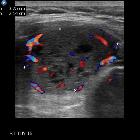

Renal

carcinoma metastasis in thyroid gland mimicking a benign goitre. Transverse sonogram with colour flow showing mainly peripheral vascularity and only minimal internal vascularity of the thyroid lesion.